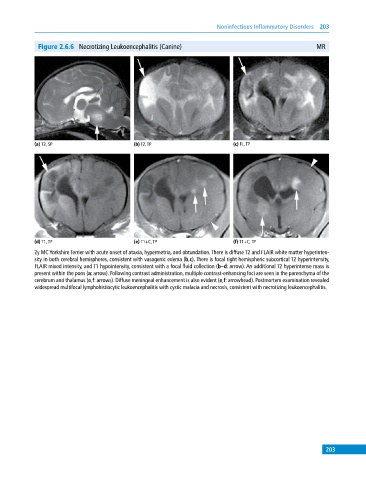

Figure 2.6.6 Necrotizing Leukoencephalitis (Canine) MR

(a) T2, SP (b) T2, TP (c) FL, TP

(d) T1, TP (e) T1+C, TP (f) T1+C, TP

2y MC Yorkshire Terrier with acute onset of ataxia, hypermetria, and obtundation. There is diffuse T2 and FLAIR white matter hyperinten

sity in both cerebral hemispheres, consistent with vasogenic edema (b,c). There is focal right hemispheric subcortical T2 hyperintensity,

FLAIR mixed intensity, and T1 hypointensity, consistent with a focal fluid collection (b–d: arrow). An additional T2 hyperintense mass is

present within the pons (a: arrow). Following contrast administration, multiple contrast‐enhancing foci are seen in the parenchyma of the

cerebrum and thalamus (e,f: arrows). Diffuse meningeal enhancement is also evident (e,f: arrowhead). Postmortem examination revealed

widespread multifocal lymphohistiocytic leukoencephalitis with cystic malacia and necrosis, consistent with necrotizing leukoencephalitis.